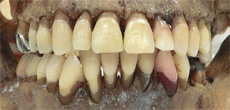

Digital Dental Chart

写真および歯の番号をクリックすることで詳細な画像・情報を見ることができます。

歯科所見の特徴点としては、「上顎左右側側切歯の矮小歯様形態」「上顎左右側第二小臼歯,下顎左側第一小臼歯根尖の近心への湾曲」「上顎左側第一大臼歯,同第二大臼歯の挺出」「下顎左右側犬歯の近心傾斜および捻転」「下顎右側第一大臼歯の仮封材(治療途中の可能性)」が挙げられる。

5432|234567 : エナメル質内の咬耗

1|121|12 : 咬耗による象牙質の露出

2| : 斜切痕の存在、  |67|6 : 挺出

2|2 : 根尖が遠心に湾曲、   5|5|4 : 根尖が近心に湾曲